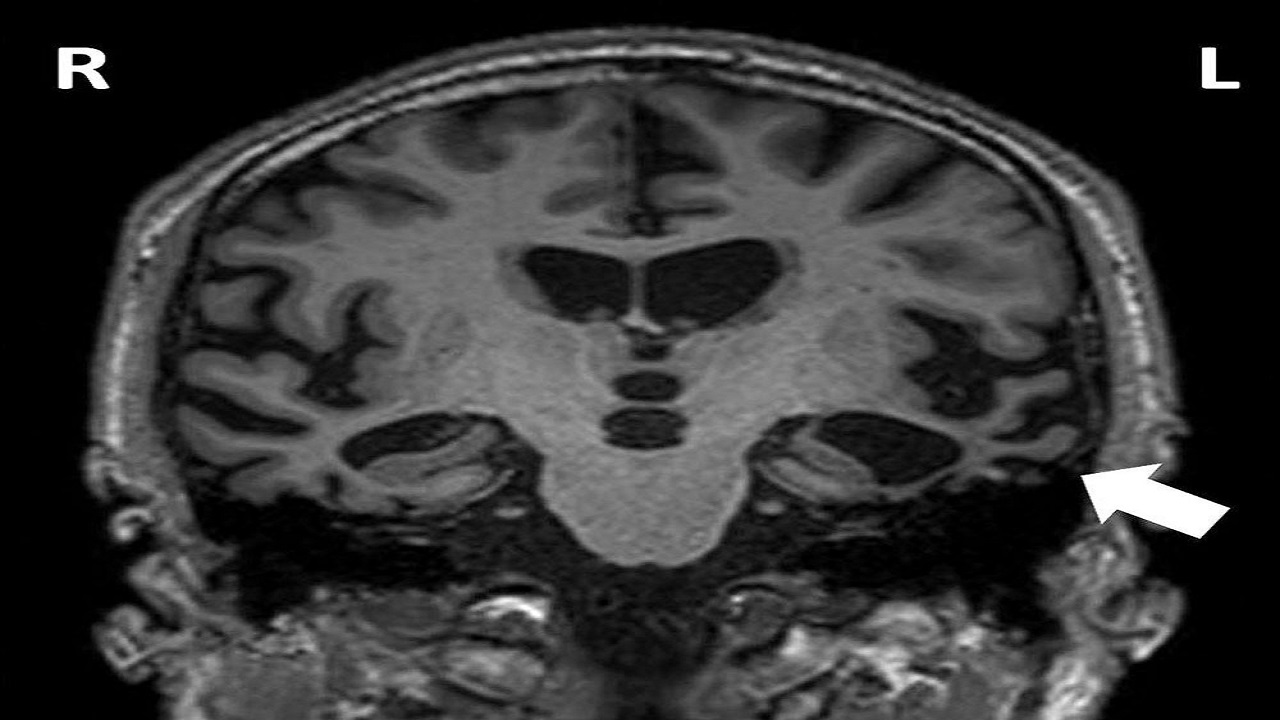

يعد مرض التصلب العصبي المتعدد Multiple Sclerosis التهاباً مزمناً يصيب الجهاز العصبي المركزي، وأسبابه غير معلومة على وجه الدقة حتى الآن، ولكن يرجح الأطباء أنه يرجع إلى أحد أمراض المناعة الذاتية؛ إذ يهاجم جهاز المناعة الدماغ والنخاع الشوكي، حسب الجمعية الألمانية لمرض التصلب العصبي المتعدد.

وأضافت الجمعية أن أعراض الإصابة بالتصلب المتعدد تتنوع اعتماداً على المناطق المصابة بالالتهاب المزمن؛ لذا يُعرف مرض التصلب العصبي المتعدد باسم مرض الألف وجه، ما يجعل التشخيص صعباً.